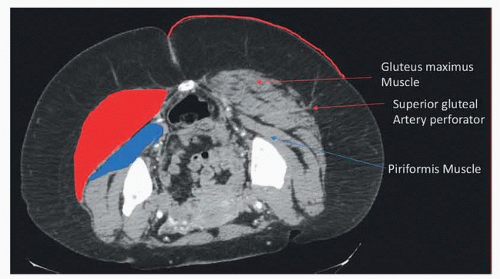

Perforators should be described as they exit the deep muscular fascia and described based on location in an x–y axis. The gluteal fold will be set as zero on the y-axis, and the midline will be set as zero on the x-axis. Important bony landmarks that should be noted include the coccyx, the summit of the posterosuperior iliac crest, and the most lateral point of the greater trochanter7 (FIG 3).

FIG 3 • Locations of SGAP perforator on axial CT scan including the gluteus maximus muscle and piriformis muscle.